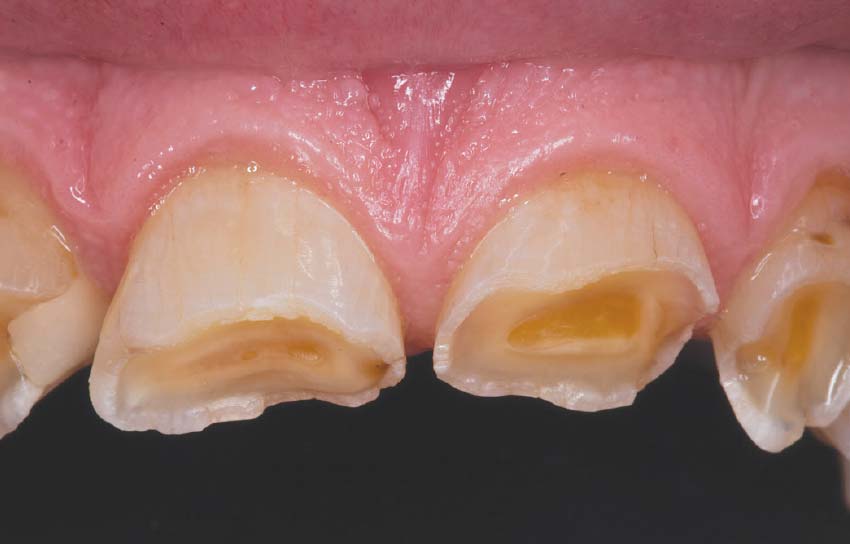

1. Tooth Erosion

Stomach acids are highly corrosive. When they reach the mouth , they can start to erode tooth enamel – the hard , protective outer layer of your teeth. Enamel erosion is irreversible and can lead to :

• • Increased tooth sensitivity

• • Yellowing of teeth

• • Higher risk of cavities

• • Chipping and cracking